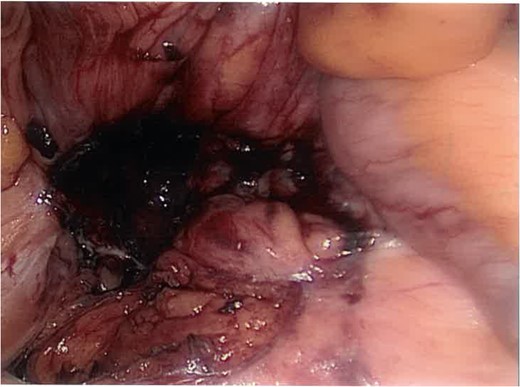

The stone was retrieved (Fig. 4) and the cavity debrided and washed-out. Figure 3 shows the same cavity following excision of the offending stone.

Post-excision laparoscopic view of the posterior abdominal wall cavity.